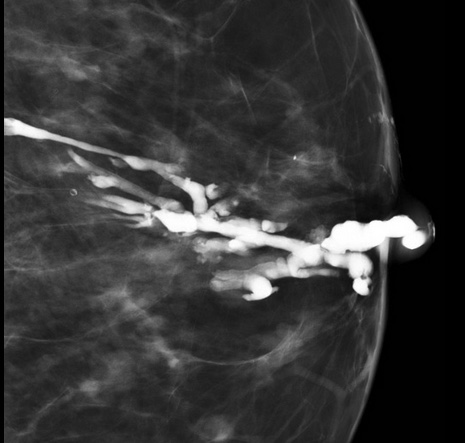

Ectasie Canlaire Solitaire

- Rare

ductal duct ectasia canal canalaire ectasiante

Ectasie Canlaire Solitaire

ductal duct ectasia canal canalaire ectasiante